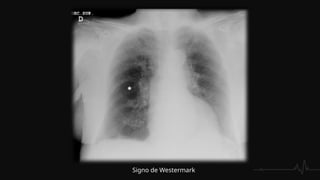

HALLAZGOS RADIOGRÁFICOS

RADIOGRAFÍA DE TORAX

 Ensanchamiento de la silueta cardiomediastínica, debido al aumento del

calibre de las arterias centrales.

 Infarto pulmonar. Se observa un infiltrado alveolar localizado , en forma de

cuña, triangular y de base pleural, generalmente basal, con borde inferior

convexo (joroba de Hampton)

 Signos de Wetsermark: área de enfisema local causado por un defecto

en la perfusión que con leva una hiperclaridad marcada.

 Signo de Fleischner: dilatación de la arteria debido a la impactación del

émbolo.

 Atelectasias laminares basales con elevación del hemidiafragma

 Derrame pleural

Joroba de Hampton Signo de Fleischner

Signo de Westermark

RADIOGRAFÍA DE TORAX Ensanchamiento de la silueta cardiomediastínica, debido al aumento del calibre de las arterias centrales.  Infarto pulmonar. Se observa un infiltrado alveolar localizado , en forma de cuña, triangular y de base pleural, generalmente basal, con borde inferior convexo (joroba de Hampton)  Signos de Wetsermark: área de enfisema local causado por un defecto en la perfusión que con leva una hiperclaridad marcada.  Signo de Fleischner: dilatación de la arteria debido a la impactación del émbolo.  Atelectasias laminares basales con elevación del hemidiafragma  Derrame pleural

Joroba de HamptonSigno de Fleischner